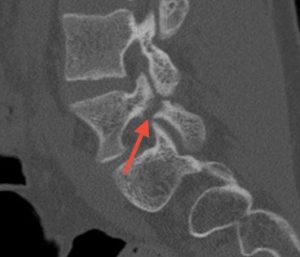

FM: Pars fracture repair is a very exciting area in spine surgery, particularly for younger patients and athletes, because it offers the ability to treat the source of pain while preserving motion. My focus has been on applying robotic technology to direct pars repair in carefully selected patients. As the highest-volume surgeon in New Jersey performing outpatient robotic pars repairs, I am currently studying my outcomes. We’re seeing that robotics can transform what was traditionally a more invasive procedure—often requiring 1-2 night hospital stays—into an outpatient surgery using small percutaneous incisions.

Patients are returning to sports as early as six to eight weeks post-operatively. While long-term comparative data is still evolving, robotics may improve reproducibility, shorten recovery, and maintain similar healing rates and long-term outcomes compared to traditional open techniques.

Images show pre-op CT and post-op CT, showing the healing, as well as a picture of the incisions. Image credits: Dr. Farah Musharbash

FM: Thankfully I have had many highlights, and every patient story is meaningful. One was performing an emergency surgery on a young patient who was paralysed from a spontaneous epidural hematoma and seeing him walk into my office unassisted two weeks later. Another was a 15-year-old athlete going home the same day after robotic pars repair—and later returning to soccer within three months. Those moments are incredibly meaningful.